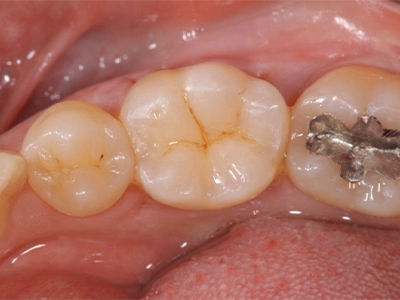

治療前後写真

治療前

治療後

年齢・性別

28歳・女性

来院理由

銀歯が取れて少ししみる

治療内容

マイクロスコープ下でカリエス除去

コンポジットレジン充填(溝に着色レジンを用いて形態・色調再現)

治療期間

1日(約60分)

費用

35,000円

リスク・副作用

補綴の再治療は歯髄損傷リスクが高まる

残存歯質が少ない場合は歯の破折リスク

医院コメント

小範囲の欠損に対して1回法で審美的に修復。

清掃性と見た目を両立。